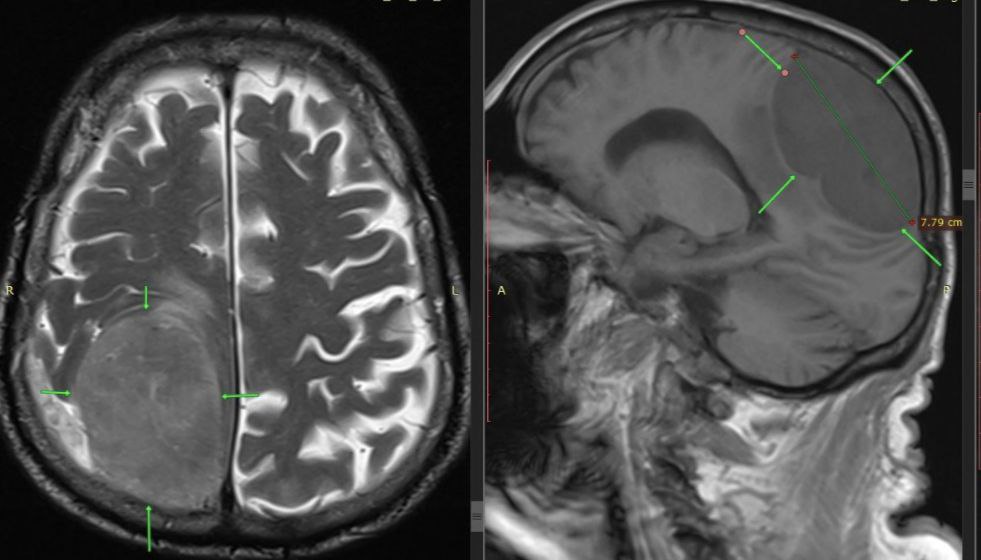

Когда 85-летний мужчина поступил в больницу у него уже отказала левая нога и левая половина тела. Изначально врачи подозревали инсульт. Но после проведеденного экстренного обследования, выяснилось, что его жизни угрожает опухоль размером 8x7 см.

Мужчине провели срочную операцию. Нейрохирурги Пятигорска выполнили трепанацию черепа и полностью удалили опухоль.